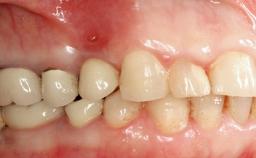

A 73-year-old woman was referred to the Division of Periodontology (University of Geneva School of Dental Medicine) after repeated unsuccessful treatment of a peri-implant infection. She was systemically healthy and did not smoke. The patient’s history revealed that, three years earlier, an immediate implant (Straumann Tapered Effect RN 4.8/4.1; Institut Straumann AG, Basel, Switzerland) had been inserted to replace the upper right central incisor. A metal-ceramic crown had been delivered using an adhesive resin cement. One year later, the patient had consulted another dentist due to discomfort in the soft tissues in the implant region. There was a suppurating peri-implant pocket, 10 mm deep. Peri-implant bone loss and excess luting cement were seen on the radiograph. The situation was treated with non-surgical debridement, amoxicillin, and repeated submucosal irrigation with a chlorhexidine digluconate solution. The patient was referred after the suppuration had persisted for several months.